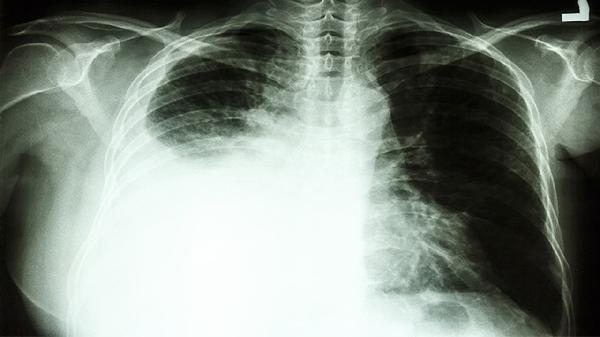

肺癌早期通過規(guī)范治療可實現臨床治愈,5年生存率可達80%以上。生存期受病理類型、分期、治療方式、患者體質、隨訪管理等因素影響。

IA期患者術后10年生存率超90%,IB期約60%。腫瘤直徑小于3厘米且無淋巴結轉移者,通過肺段切除術即可達到根治效果。微創(chuàng)胸腔鏡手術可降低術后并發(fā)癥風險。